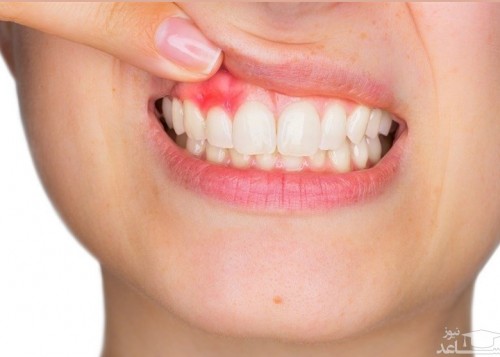

ورم و قرمزی لثه

خونریزی لث